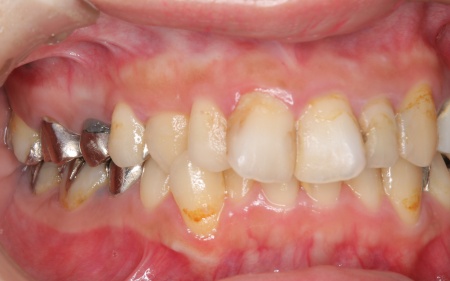

20代女性 ワイヤー矯正で歯並びを整えて虫歯治療やインプラント治療で口腔内全体を改善した症例

診断結果をお伝えしたうえで、以下2つの治療方法を提案しました。 ①歯並びを整えず、必要な部分のみを治療する方法 ②矯正治療で歯並びと噛み合わせの土台を整えたうえで、口腔内全体の治療を行う方法 それぞれのメリット・デメリットをお伝えしたところ、患者様は②の矯正治療を含めた総合的な治療を行う方法を選択されました。 はじめに、歯の表面にブラケットと呼ばれるボタン状の装置を接着し、そこにワイヤーを通して歯を動かすワイヤー矯正を開始しました。治療期間中は定期的に状態を確認し、計画通りに歯が動くよう調整を重ねています。 虫歯が生じている歯に対しては、虫歯部分を丁寧に除去し、歯の形を整えました。その後、被せ物を作製するために型取りを行い、後日完成した被せ物を装着しました。 また、欠損していた左上奥歯1本と左下奥歯1本に対しては、インプラント治療を行います。 すべての治療工程を終えたあと、噛み合わせや見た目、被せ物の使用感に問題がないかなどを確認して、治療を終了しています。 |

治療後